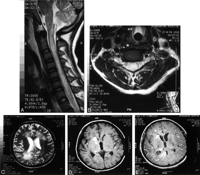

Chẩn đoán hình ảnh về thần kinh trên 11 bệnh nhân có bệnh lý GĐGTTK được báo cáo trên y văn. Chụp CT sọ não, xuất huyết dưới nhện và xuất huyết nội sọ là các hình ảnh hay gặp. Trên một bệnh nhân phát hiện có xuất huyết dưới màng cứng. Dấu đặc trưng của bệnh lý giun đầu gai ở não trên phim chụp MRI là phát hiện vết xuất huyết (track). Dấu hiệu cộng hưởng từ của thương tổn xuất huyết thay đổi tùy theo các tổn thương thể cấp, bán cấp và mạn tính. Do đó, trên hình ảnh T1 và T2 cả giảm tỷ trọng và tăng tỷ trọng đều phát hiện. Không thấy di chứng gradient-echoT2 được báo cáo. Tuy nhiên, dấu hiệu này rất nhạy với các các khối máu tụ tại chỗ không đồng nhất và có thể trở thành một chuỗi tiếp nối trong đánh giá chẩn đoán hình ảnh của bệnh giun đầu gai thể não.

Sưng phồng tủy sống đa đoạn lan tỏa kèm theo tăng tỷ trọng T2 là hình ảnh hay gặp nhất trên chụp tủy sống. Tăng gadolinium của các thương tổn được báo cáo trong phim MRI chụp sọ não và tủy sống của 4 bệnh nhân như là hình ảnh nốt, sáng và đồng nhất.

Bảng 2. Đặc điểm chẩn đoán hình ảnh trên thần kinh của bệnh giun đầu gai thể thần kinh

Vị trí | Phương thức chẩn đoán | Hình ảnh thần kinh |

Não bộ | CT | Nhu mô não (đơn điểm hoặc đa điểm) tăng tỷ trọng vùng dưới màng cứng hoặc dưới màng nhện tương ứng với xuất huyết trong não |

| MRI | Đa điểm (giống giun) tăng tỷ trọng T2 hoặc giảm tỷ trọng trong cả hai bán cầu não và tiểu não đường kính ≥ 3mm (vệt xuất huyết) có hoặc không có tăng thành phần gadolinium. |

Tủy sống | MRI | Dãn hoặc sưng phồng tủy sống kèm theo tăng tỷ trọng đa đoạn T2, thường tăng ngấm gadolinium (nhẹ đến trung bình) trên hình ảnh sau tiêm chất cản quang T1 |

* CT_CTomputed tomography; MRI: Magnetic Resonance Imaging |